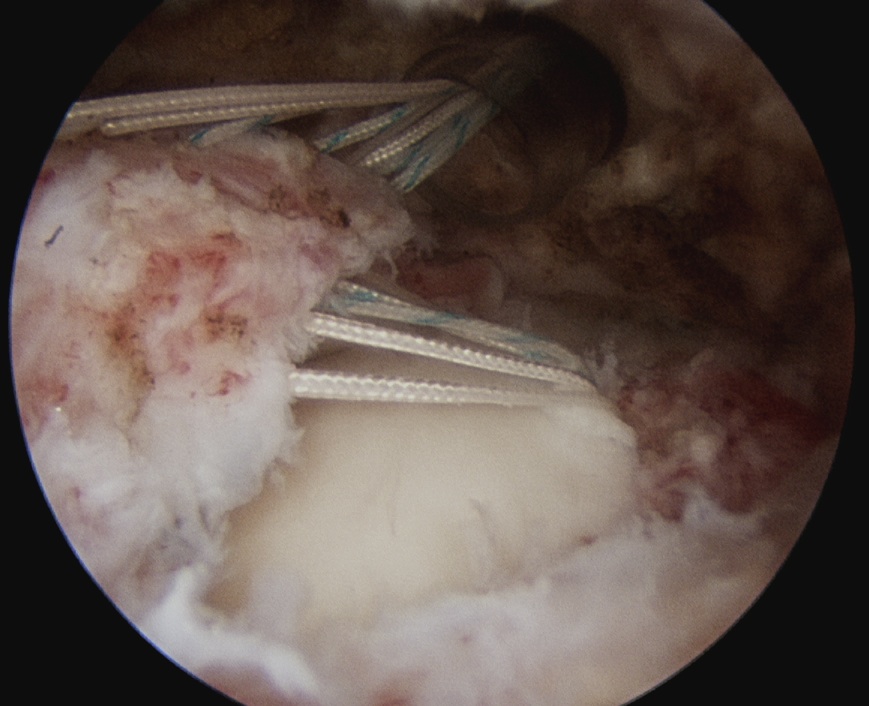

D. Transosseous equivalent / suture bridge

Technique

- biomechanically replicate tradional open transosseous

- sutures crossed as below in double row

- aiming to increase contact between cuff and footprint

Double row

- either pass second lateral row of anchors or

- use foot print anchors, retrieve previous sutures

- can make suture bridge configuration

- check repair via lateral portal